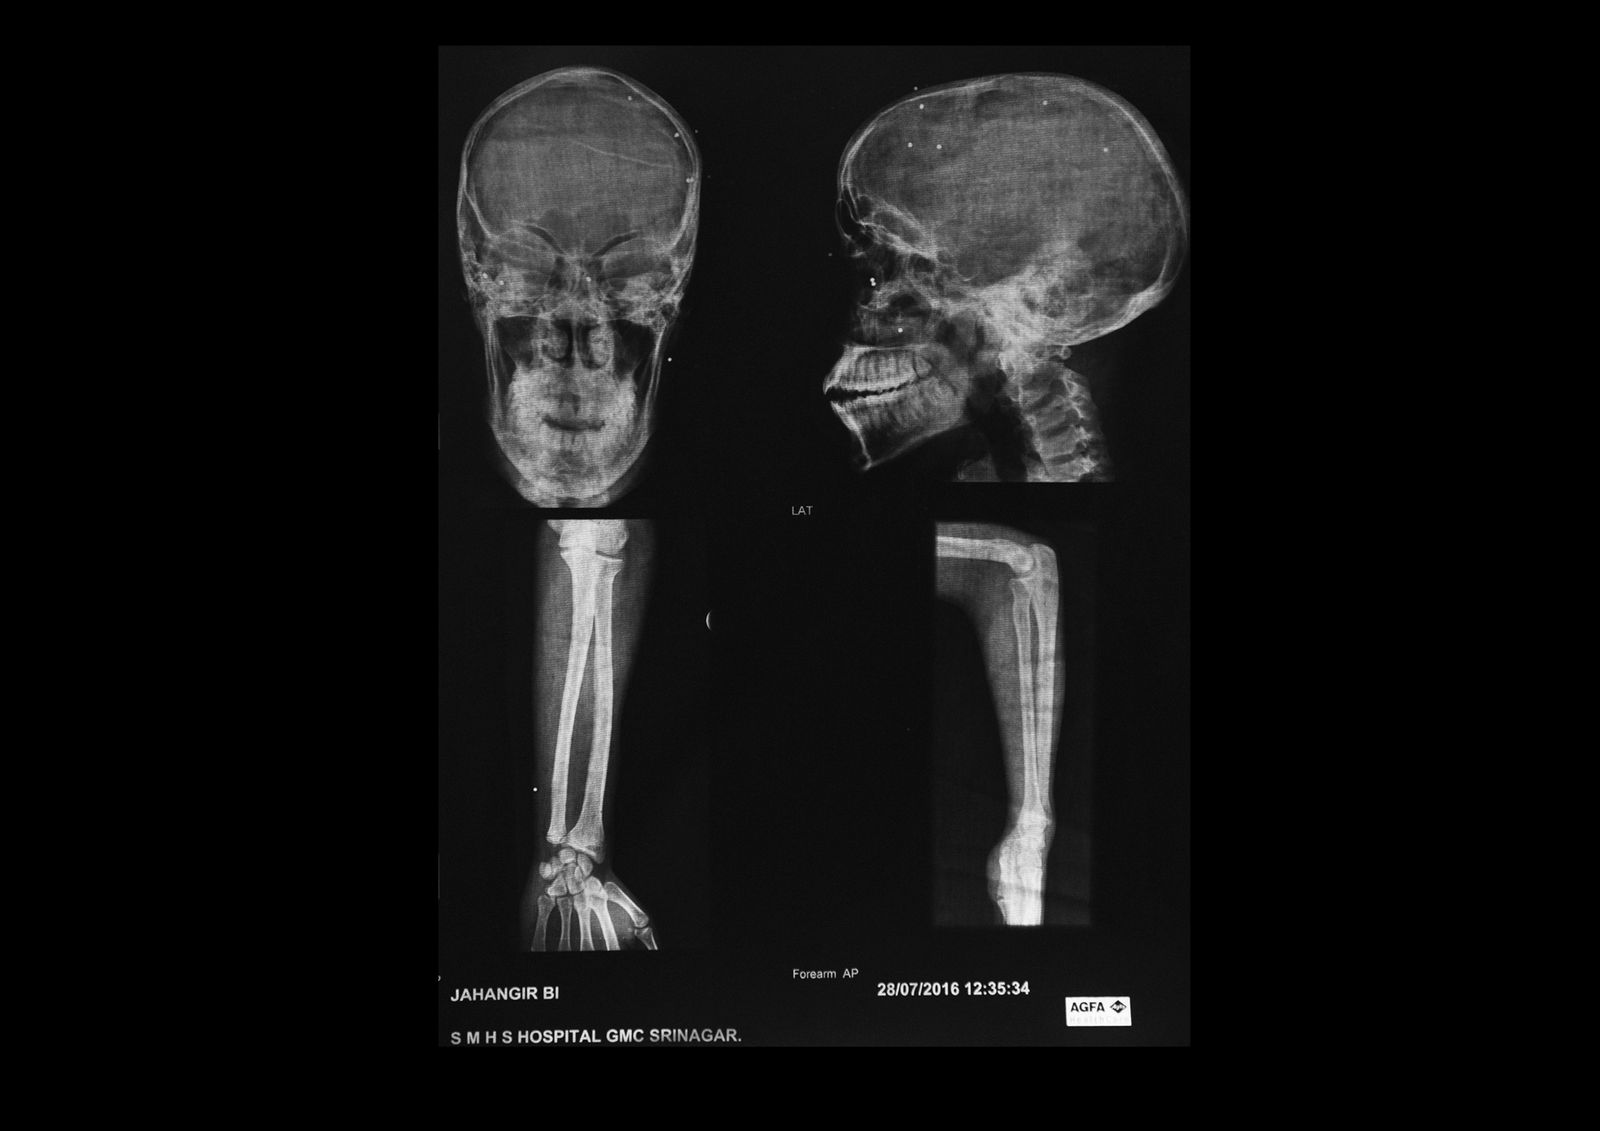

Amir Kabir Beigh, 26 years old, Baramulla. “In September 2010 i was going to buy some medicine for my mother by evening time when a group of security forces fired at me near the bridge of the old town. There had been clashes throughout the day but it was calm at that time. I was alone on the street so only after some minutes somebody found me and took me to the hospital. I have gone through a lot of surgeries all over India but i am still completely blind”. Amir is the first pellet victim of Kashmir, he received hundreds of iron balls on his body.